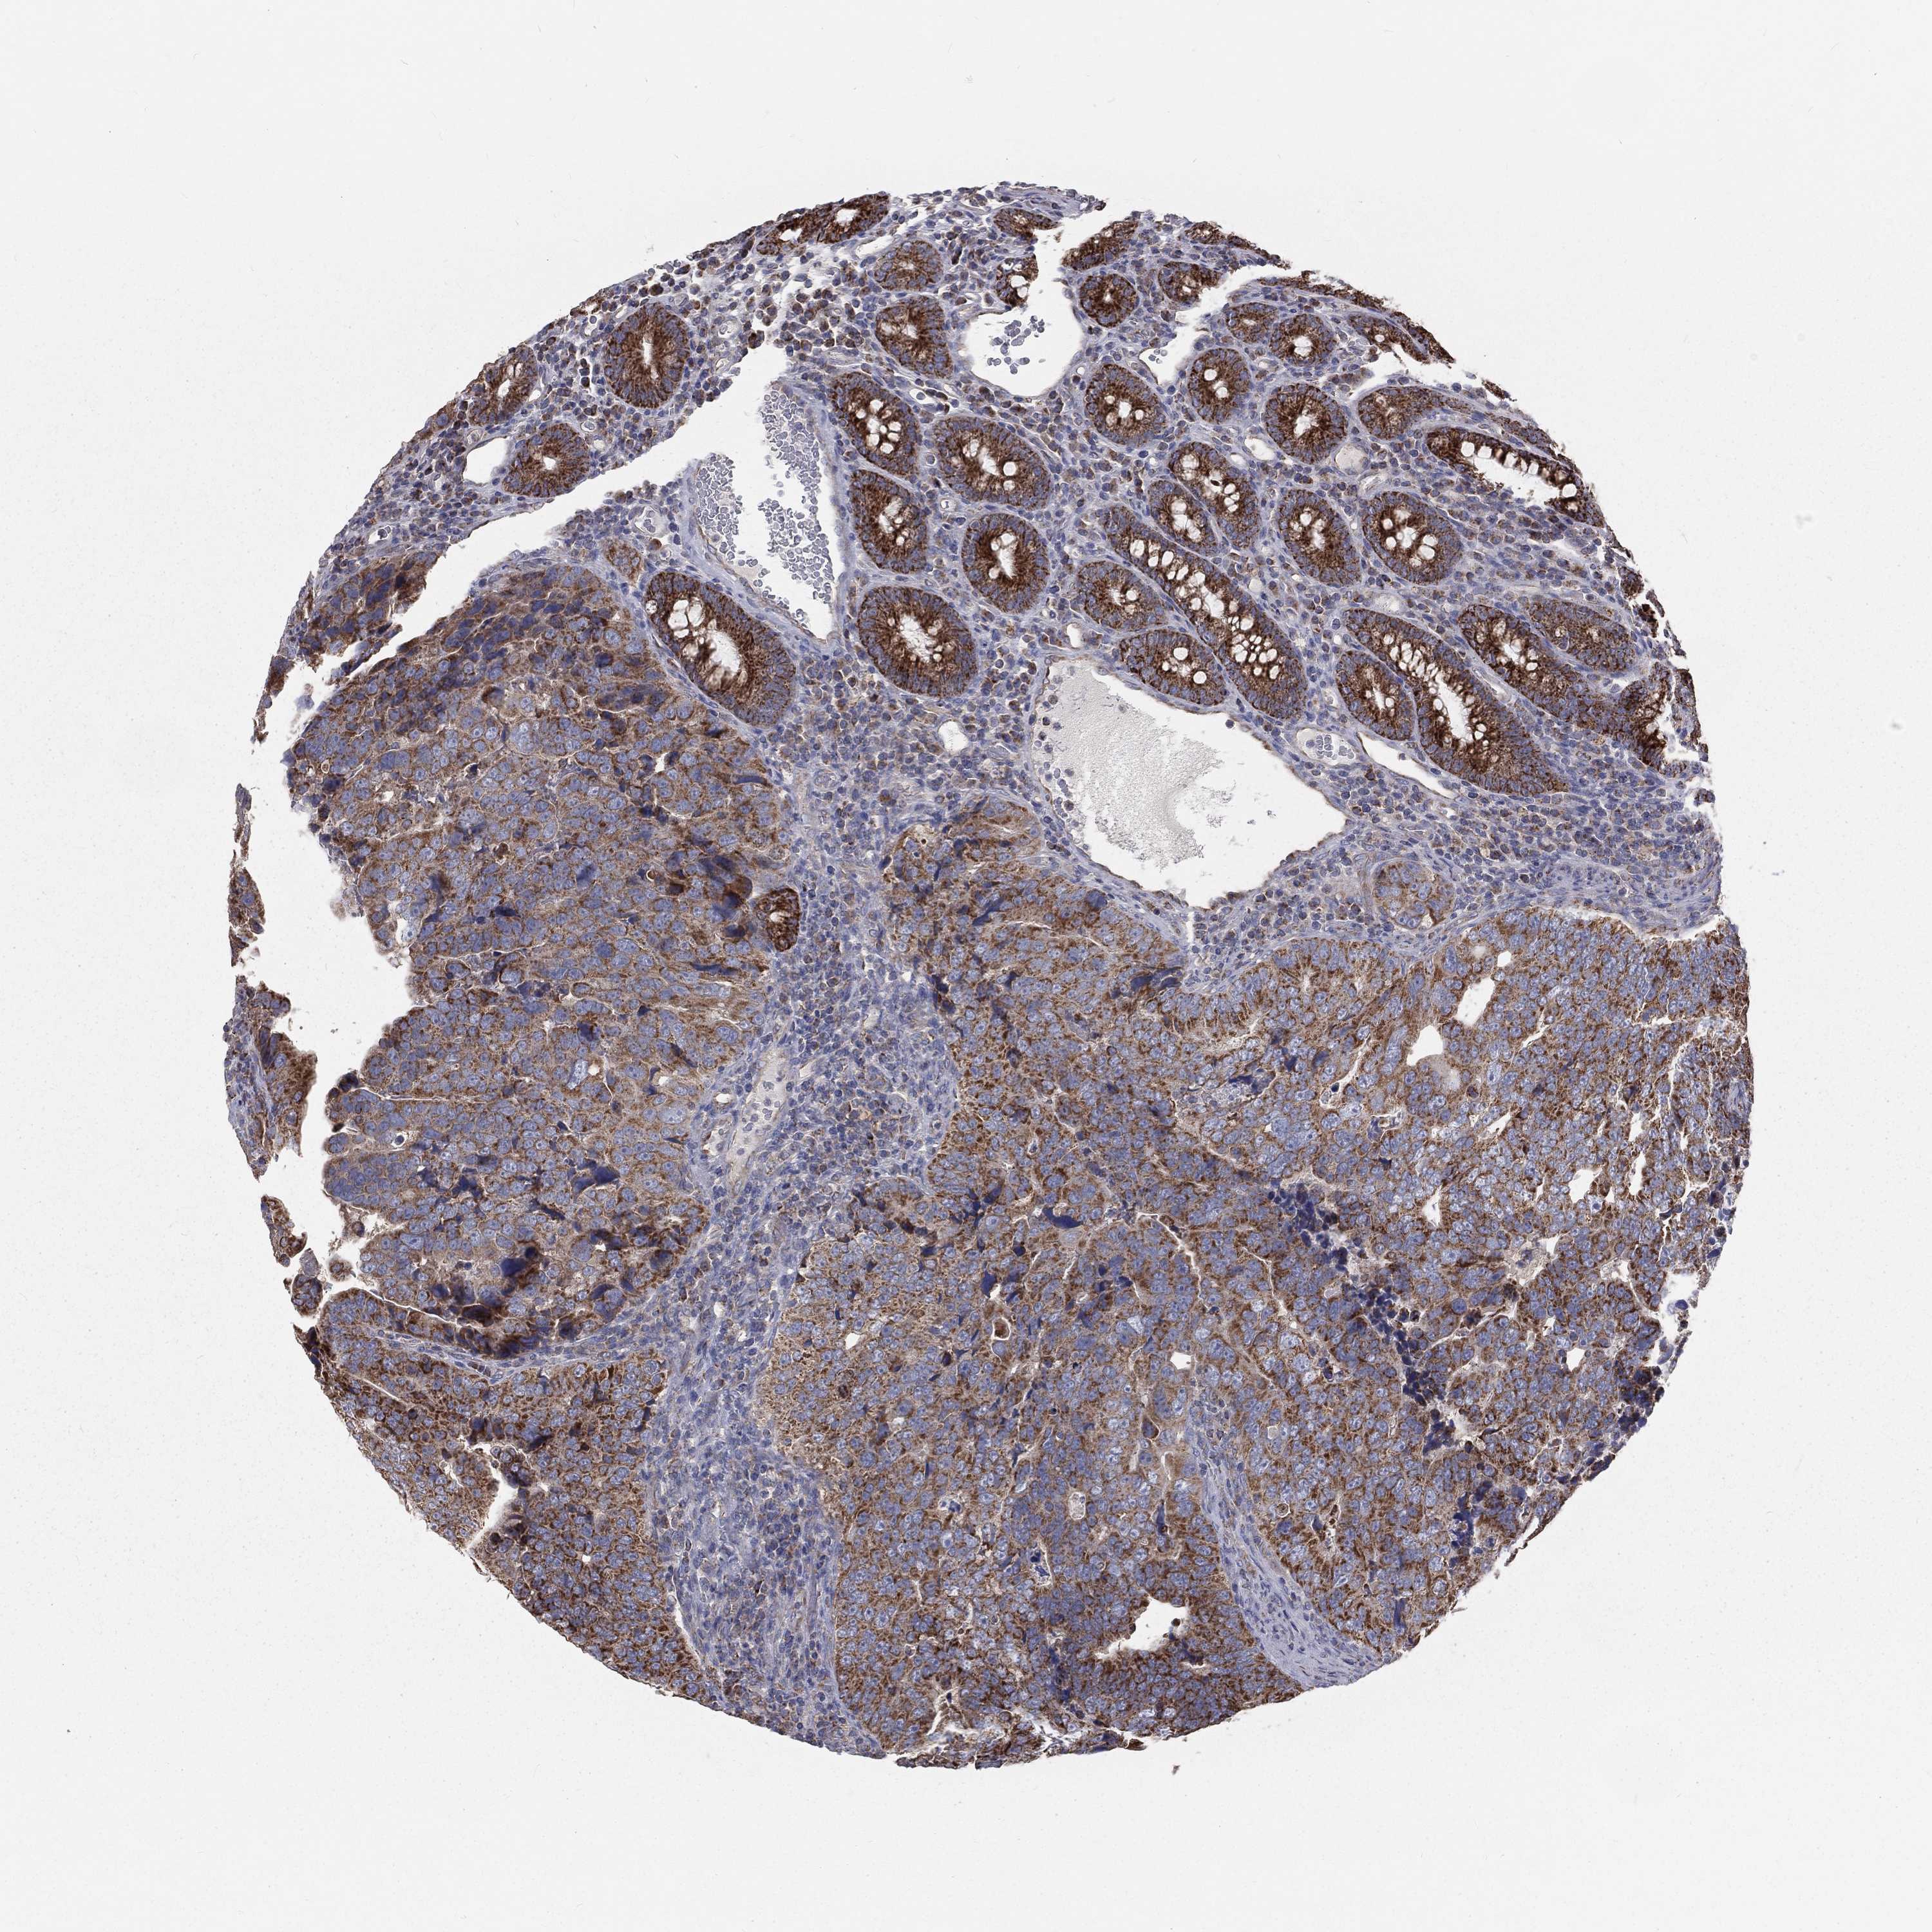

CANCER COLORECTAL CANCER Show tissue menu

Colorectal cancer

Human cancer

Colon adenocarcinoma